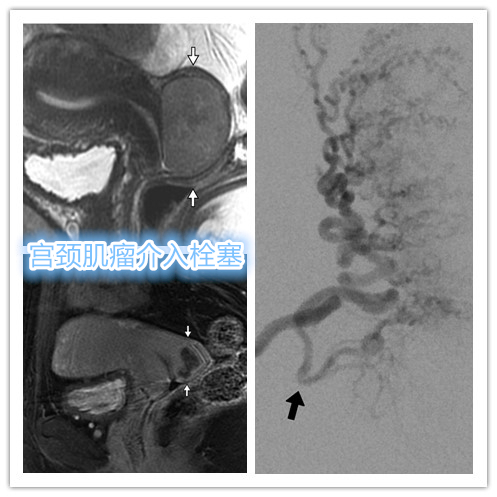

宫颈肌瘤

位于子宫颈的子宫平滑肌瘤很少见,占所有子宫平滑肌瘤的0.9%~8%。 因宫颈部肌瘤同时存在子宫动脉分支及阴道动脉分支参与供血,另血管更为细小,导致肌瘤栓塞后坏死不完全。另有担心异位栓塞导致阴道组织缺血坏死风险。

- MRI显示多发子巨大宫肌瘤,压迫膀胱。